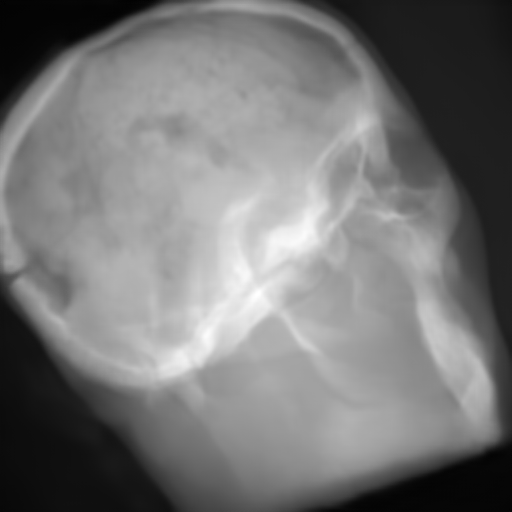

(e) Reference: X-ray proj.

(j) Reference: X-ray proj.

Figure 2: Results of the projection synthesis. Top row: Results generated with the perceptual-loss function. Bottom row: Results generated with the 1subscript1\ell_{1}-loss function.

The quantitative and qualitative results of the proposed experiments are presented in Table I and Figure 2. By examining these it can be observed that the differences in the calculated MSE of all network architectures and incorporated loss functions are only small. The best results in terms of pixel-wise deviation could be achieved with the ResNet architecture combined with the 1subscript1\ell_{1}-loss function. This network achieves a deviation from the reference of only 0.058, i.e., 2.4 percent. Also the results of the U-net and CRN networks are still good with deviations of 2.6 and 2.9 percent. Similarly small variation can be observed in the structured similarity measure. The ResNet and CRN exhibit approximately equal quality with SSIM measures of 0.938 and 0.920 for the 1subscript1\ell_{1}-loss and 0.924 and 0.931 for the perceptual-loss, respectively. The results generated with the U-net are slightly worse. The highest peak signal-to-noise ratio is achieved by the ResNet (1subscript1\ell_{1}-loss), followed by the U-net (1subscript1\ell_{1}-loss) and CRN (p-loss). It is noteworthy that the ResNet and U-net both achieve the highest results in all error metrics using the 1subscript1\ell_{1}-loss while the opposite is the case for the CRN which works best with the perceptual-loss function.

Another observation is that the perceptual-loss is able to conserve high-frequency details in the image. The fine line in the projection images that forms a circle around the cranium is visible in the input (Figures 2a & 2f), as well as in the label images (Figures 2e & 2j), and also in the images generated with the perceptual-loss function (Figures 2b2c, and 2d). In contrast, all generators ”loose” this line when the 11\ell 1-loss is applied (Figures 2g2h, and 2i). This effect is also qualitatively observable in other parts of the images. Despite achieving equal or better results regarding the error metrics, the generally less sharp look of the results generated with the 11\ell 1-loss function is apparent. This behavior is in accordance with previous observations that concluded that an perceptual-loss leads to sharper images than a comparable 11\ell 1-loss [19]. Considering the common applications of X-ray Fluoroscopy, e.g., interventional guidance for stents and similar devices, high spatial resolution is a key requirement. Utilizing a loss function that is able to preserve high-frequency details in the images is desirable to this end. The perceptual-loss appears to be suited for this task as presented in our evaluation.